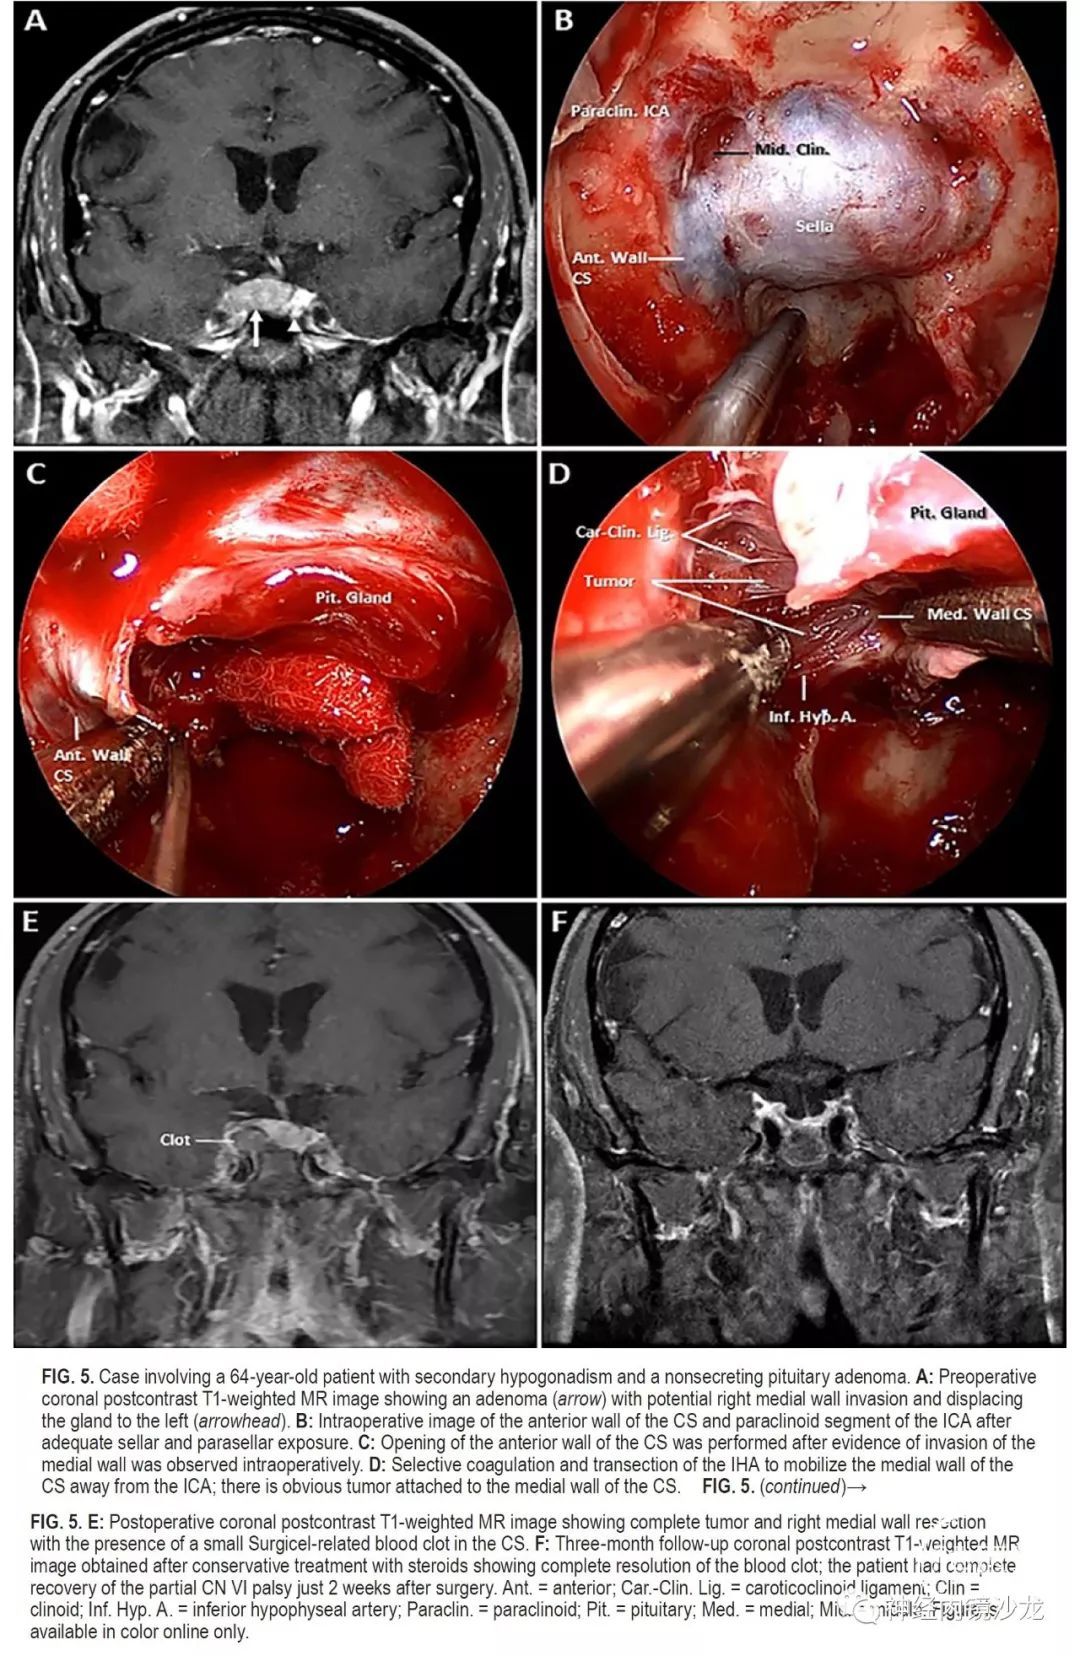

目的:垂体腺瘤常侵袭海绵窦(CS)的内侧壁,但由于存在血管和颅神经损伤的风险,通常不能外科手术切除。本研究的目的是报告一组大宗采用基于解剖学基础、分步选择性地手术切除海绵窦内侧壁的侵袭性垂体腺瘤病例的手术结果。

方法:对作者所在机构数据库进行了研究分析,筛选术中发现单纯侵犯内侧壁且采用内镜经鼻入路选择性切除海绵窦内侧壁的垂体腺瘤病例。排除侵袭海绵窦超出内侧壁的病例。对患者的并发症、切除率和缓解率进行评估。

结果:50例患者符合本研究的条件,15例(30%)非功能性腺瘤和35例(70%)功能性腺瘤;包括16例生长激素、10例催乳素和9例促肾上腺皮质激素(ACTH)腺瘤。非功能性腺瘤的平均肿瘤大小为2.3cm,功能性腺瘤的平均肿瘤大小为1.3cm。放射学检查,11例(22%)为Knosp 1级,23例(46%)Knosp 2级,16例(32%)Knosp 3级。根据术中判断和术后MRI,所有病例均实现肿瘤全切。对于功能性腺瘤患者,平均随访时间为30个月(范围4-64个月),对于非功能性腺瘤患者,平均随访时间为16个月(范围4-30个月)。根据最后一次随访结果,34例(97%)功能性腺瘤未采用辅助治疗即获得完全生化缓解(使用现行标准)。非功能性腺瘤的患者,未见影像学复发。50名患者中共切除了57侧内侧壁。组织学证实,93%的非功能性腺瘤和83%的功能性腺瘤中存在内侧壁侵袭。没有死亡或颈内动脉损伤病例,平均失血量为378ml。4名患者(8%)出现新发短暂性颅神经麻痹,其中2名患者需要再次手术清除血凝块和脂肪填塞物。未出现永久性颅神经麻痹。

结论:海绵窦内侧壁可以安全有效地切除,并发症低,完全切除和症状缓解率极佳。这种基于解剖学的手术技术的长期疗效,需要更多随访数据进一步确定。该技术只能由非常有经验的鼻内镜颅底团队进行。